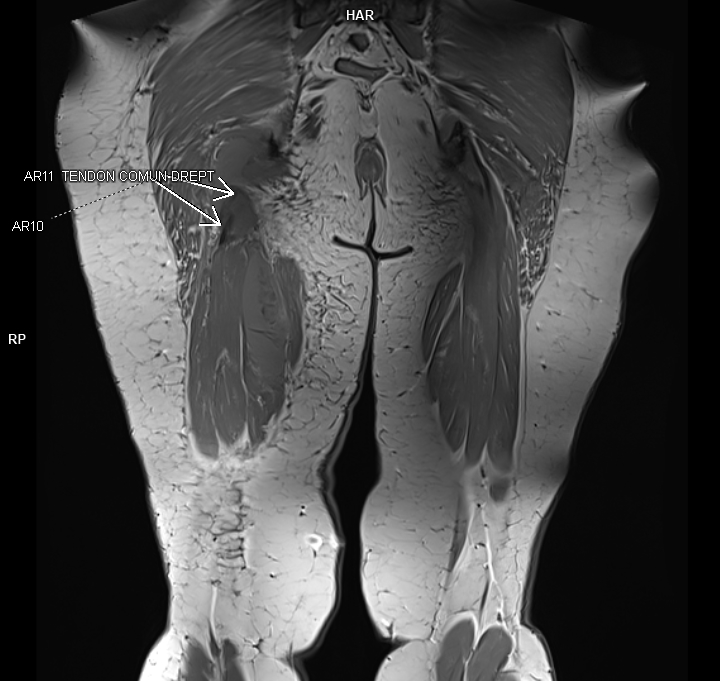

Figurile 1 si 2: coronal T1 coapsă bilateral

Discuţie caz nr 92: Harmstring lesion este dificil de tradus în limba română și se referă la leziunea celor trei mușchi ce se inseră pe tuberozitatea ischiadică: semitendinos, semimebranos și biceps femural. Cazul prezentat este a unui pacient care s-a aplecat la cumpărături să ridice o plasa și a simțit o durere puternică în spatele coapsei urmată de impotența funcțională si de creștere de volum a coapsei posterior. Pe imaginile postate se evidențiază avulsia tendonului comun al celor trei muschi ce se regăsește retractat inferior cu formarea unui hematom în vecinătate.